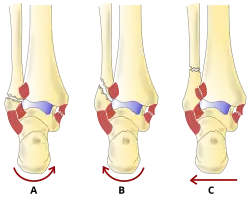

- La classification de Lauge-Hansen (en) classe les fractures selon le mécanisme de la blessure en fonction de la position du pied et de la force de déformation (le type le plus courant est la supination-rotation externe).

- La classification Danis-Weber (en) classe les fractures de la cheville selon le niveau de la fracture de la fibula distale (type A = en dessous du ligament syndesmotique, type B = à son niveau, type C = au-dessus du ligament), avec une utilisation dans l'évaluation des lésions de la syndesmose et la membrane interosseuse.